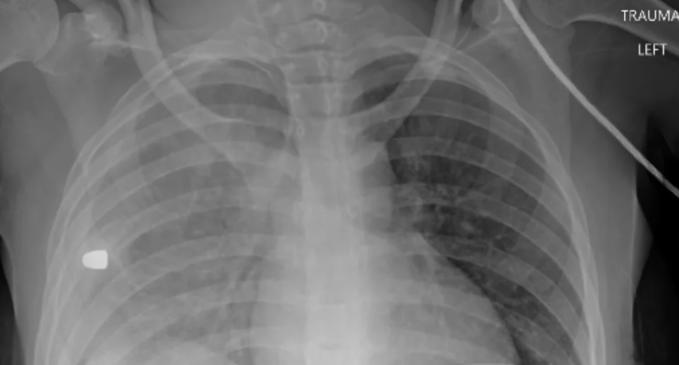

Ảnh X-quang tiết lộ nguyên nhân khiến nhiều trẻ em Mỹ tử vong. Ảnh chụp X-quang được một bác sĩ chia sẻ cho thấy các sự cố liên quan súng đạn là nguyên nhân gây tử vong hàng đầu cho trẻ em Mỹ.

Hôm 28/3, bác sĩ Sam Ghali, làm việc tại khoa Cấp cứu, Trung tâm Y tế Đại học Toledo, đă đăng bức ảnh chụp X-quang lồng ngực của một thiếu niên lên Twitter, cho thấy phổi của bệnh nhân dường như có dị vật. Ông đề nghị mọi người đoán nguyên nhân.

"Đây là phim chụp X-quang lồng ngực của một thiếu niên đang phải gánh chịu một t́nh trạng - hiện là nguyên nhân gây tử vong số một ở trẻ em và thanh thiếu niên Mỹ. Bạn hăy thử chẩn đoán xem?", ông đặt câu hỏi.

Sau đó, vị bác sĩ tiết lộ dị vật trong phim chụp X-quang này là một viên đạn, găm vào lồng ngực thiếu niên sau sự cố liên quan súng đạn. Danh tính nạn nhân không được tiết lộ. Theo bác sĩ Ghali, đây cũng là nguyên nhân số một khiến nhiều trẻ em Mỹ qua đời trong thời gian qua.

Mảnh đạn trong ngực trái của một bé gái tại Mỹ. Ảnh: Sam Ghali

Mảnh đạn trong ngực trái của một trẻ em gái tại Mỹ. Ảnh: Sam Ghali